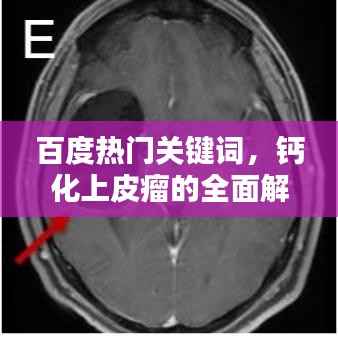

如果您怀疑自己可能患有钙化上皮瘤,最好寻求专业医生的帮助,医生会通过观察皮肤结节的外观、触摸其质地以及询问您的病史来进行初步诊断,在某些情况下,可能需要进行皮肤活检以确诊。